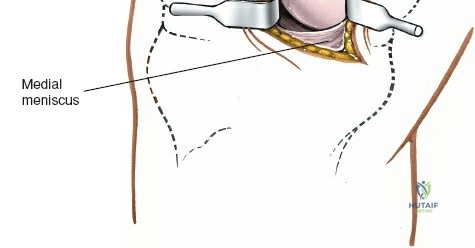

Gross Anatomy of the Medial Meniscus

The medial meniscus is a C-shaped, semilunar fibrocartilaginous structure that resides on the medial tibial plateau, acting as an interface between the femoral condyle and the tibial plateau. It is broader posteriorly than anteriorly.

- Body: The central portion, relatively immobile due to its firm attachment to the deep fibers of the medial collateral ligament (MCL) and the joint capsule via the coronary (meniscotibial) ligaments. This firm attachment, in contrast to the more mobile lateral meniscus, contributes to its higher incidence of tears, particularly in conjunction with MCL injuries.

Exposure of the Meniscus:

- Retractors are carefully placed to expose the medial tibiofemoral compartment. Self-retaining retractors may be used, but care must be taken to protect the articular cartilage.

- To improve visualization, the knee is brought into hyperflexion (as per seed content, "beyond a right angle"). This maneuver, combined with external rotation of the tibia and a valgus stress applied to the knee, widens the medial compartment. This allows for improved access to the posterior horn of the medial meniscus.

Meniscectomy Technique (Partial):

- Inspection: Thoroughly inspect the medial meniscus to identify the tear pattern and assess its stability using a blunt probe.

- Resection: The goal is partial meniscectomy, removing only the unstable, symptomatic fragment. Total meniscectomy is strongly discouraged due to long-term sequelae.

- Specialized meniscal knives (e.g., banana knife, hook knife) are used to make precise cuts, detaching the torn fragment from the stable meniscal rim and meniscocapsular junction.

- Small rongeurs or basket forceps are then used to excise the torn portion.

- The remaining meniscal edge is carefully contoured and smoothed to prevent any residual tags from impinging or causing further irritation.